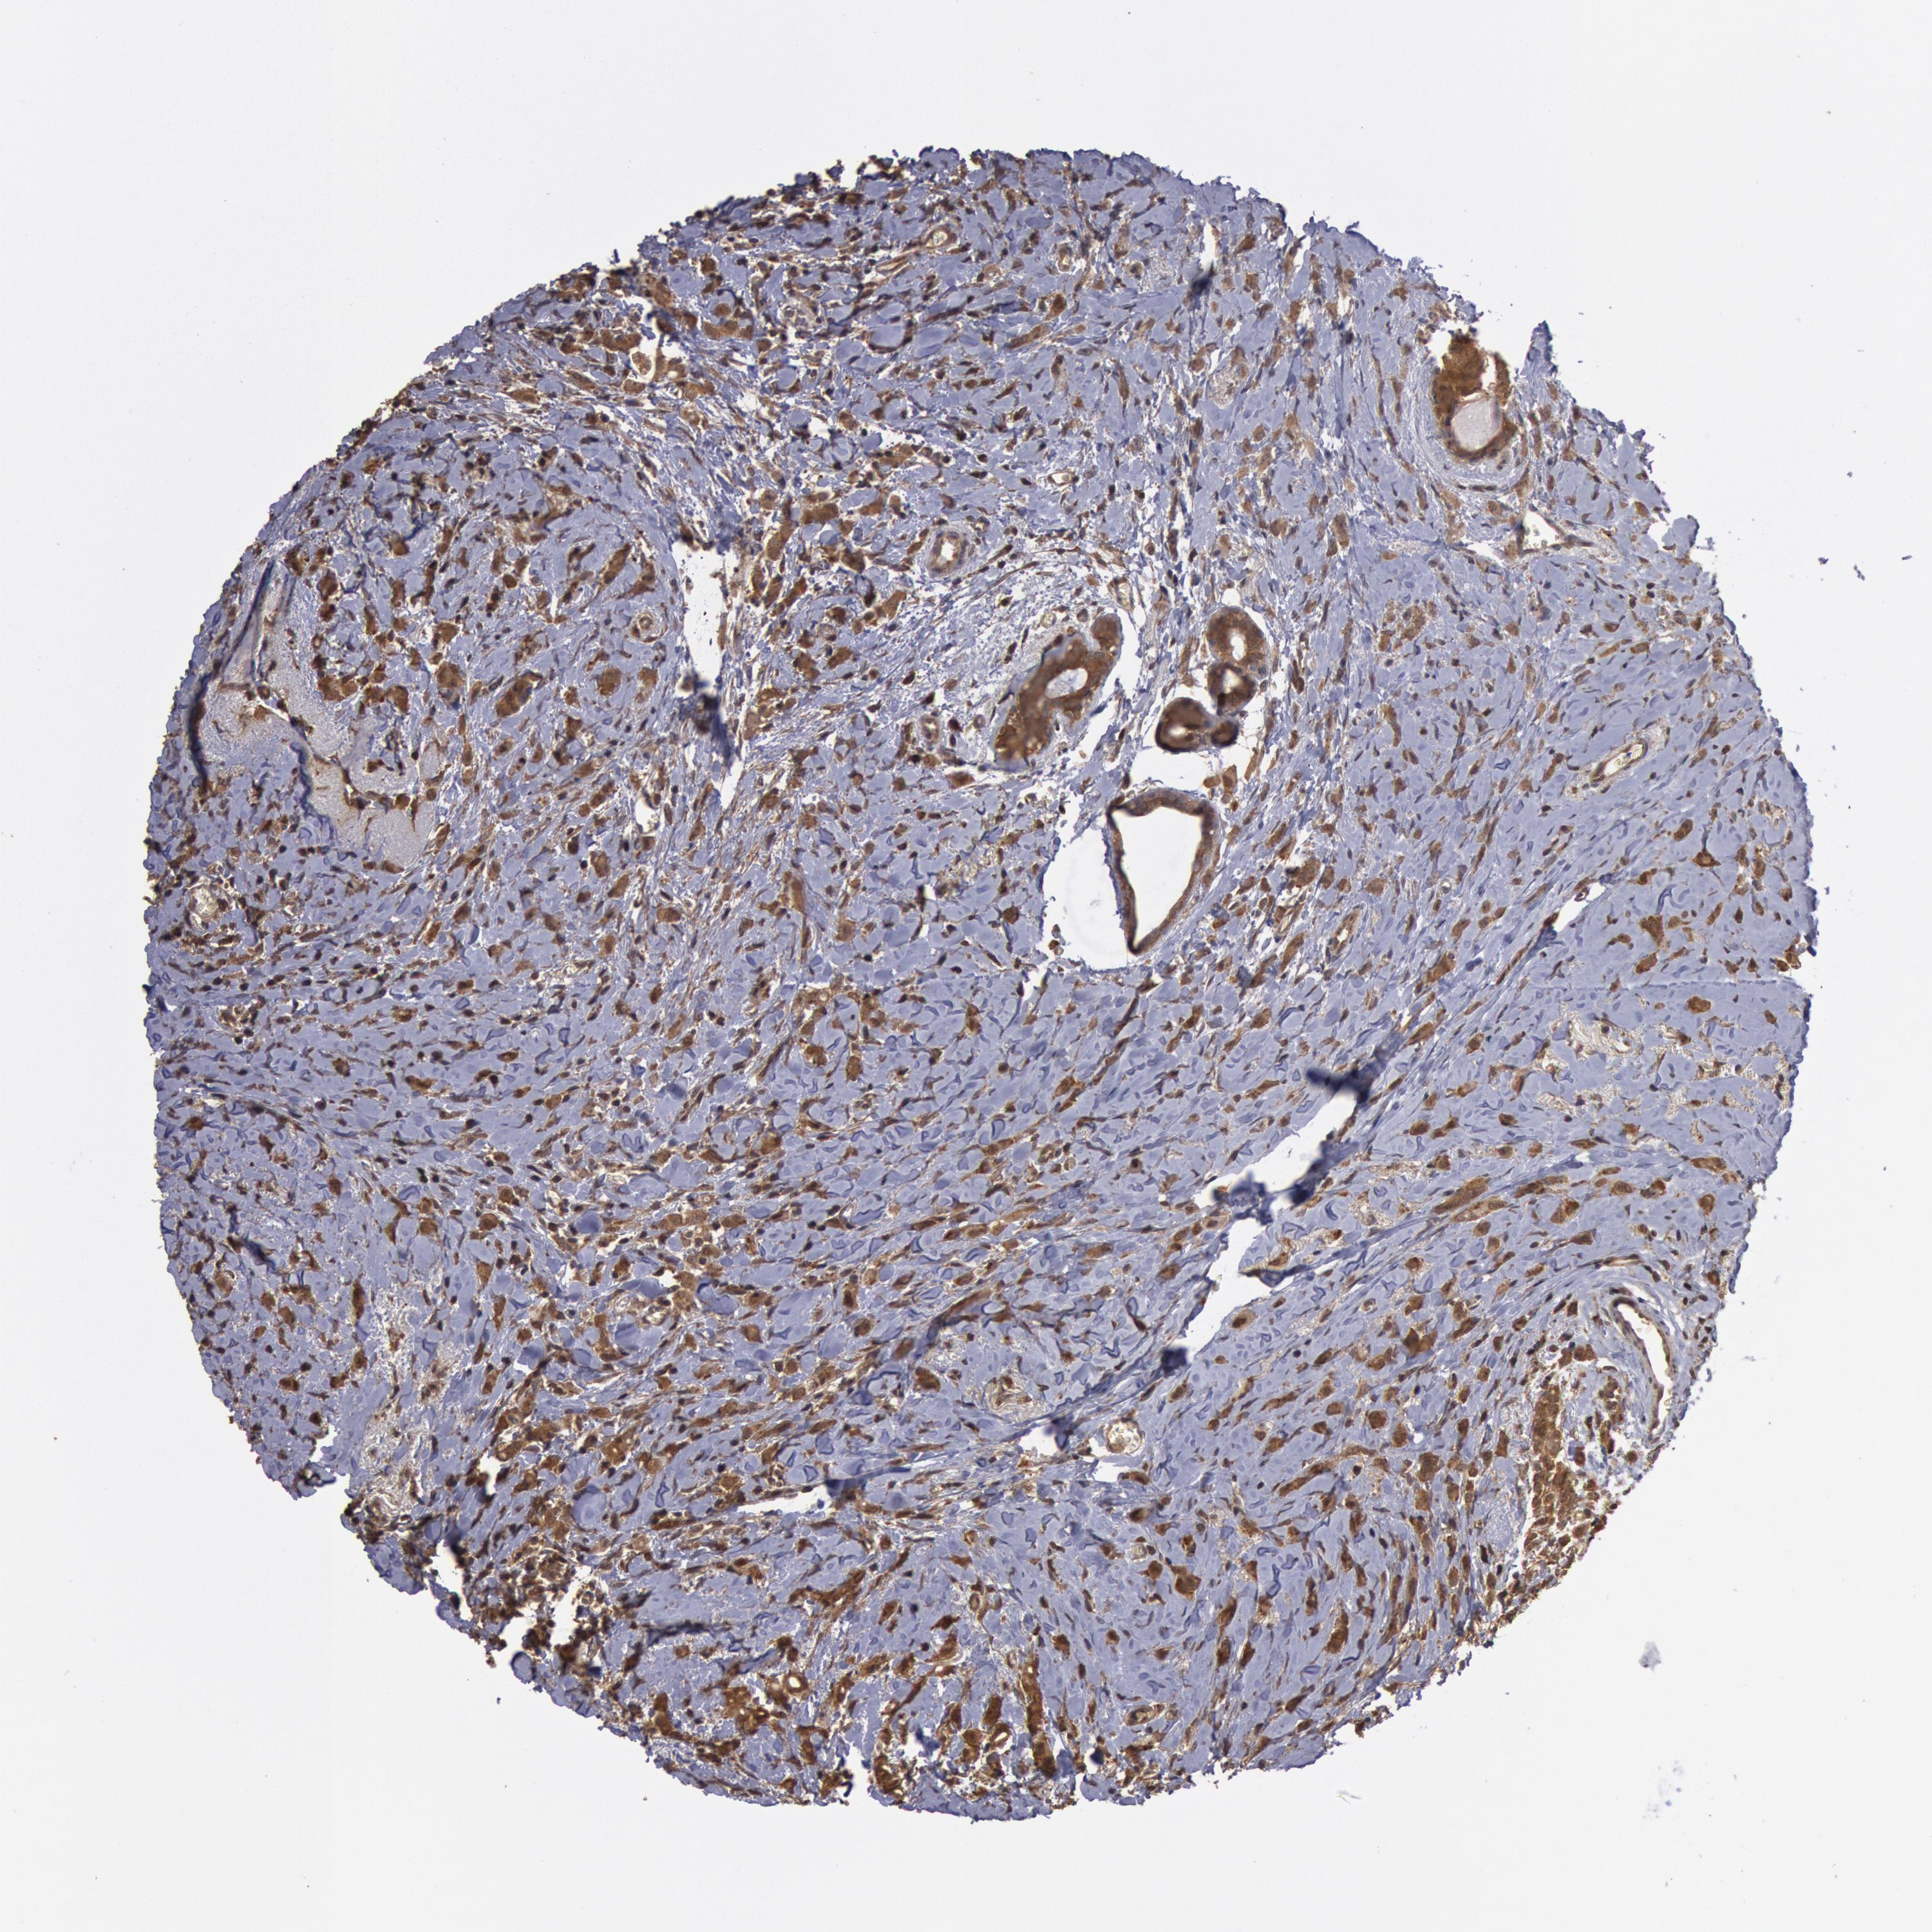

CANCER BREAST CANCER Show tissue menu

BRCA TCGA BRCA VALIDATION PROTEIN EXPRESSION

ANTIBODIES

AND

VALIDATION